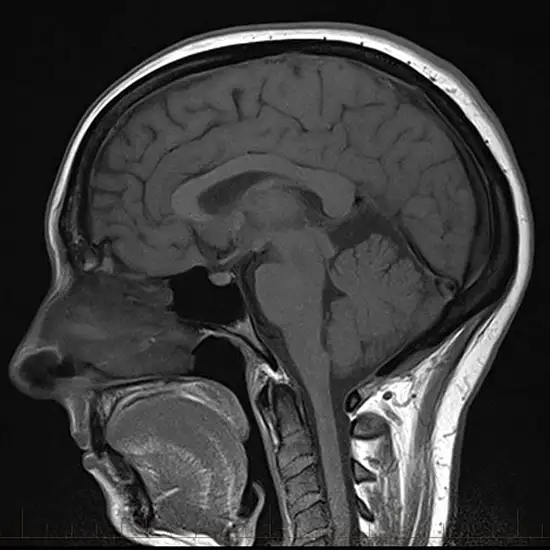

An MRI of the brain makes a picture of the bones of the brain (the cranium), the veins and arteries (grey and white matter), the cranial nerves, and the soft tissues around the brain.

MRI (Magnetic Resonance Imaging) screening of the brain is a non-invasive medical diagnostic tool used to obtain detailed images of the brain and the related tissue in the brain. MRI Screening Of the Brain is used to show abnormalities like fractures, injuries, infections, inflammations etc.